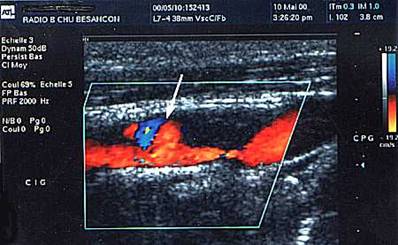

Doppler pulsatil, carotida comuna

Artera (in rosu) si vena (in albastru) vertebrala normale vizualizate in inter-transversara .

Doppler color.